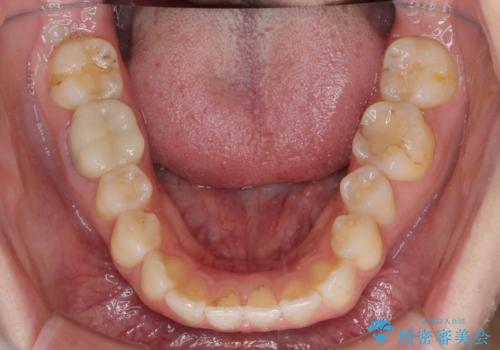

- 矯正治療の後戻りが気になるとのことで来院された患者様です。

上顎の後戻りをインビザライン・ライトで治療することとしました。

上顎のみの治療を希望されたため、咬み合わせをしっかりと改善することはできませんでしたが、審美面が大きく改善され、日常生活の機能面でも不具合を感じることはなく、大変満足していただきました。